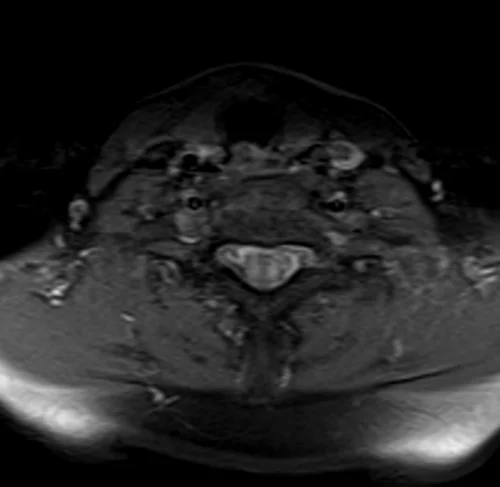

Neck MRA axial T1 fat sat images